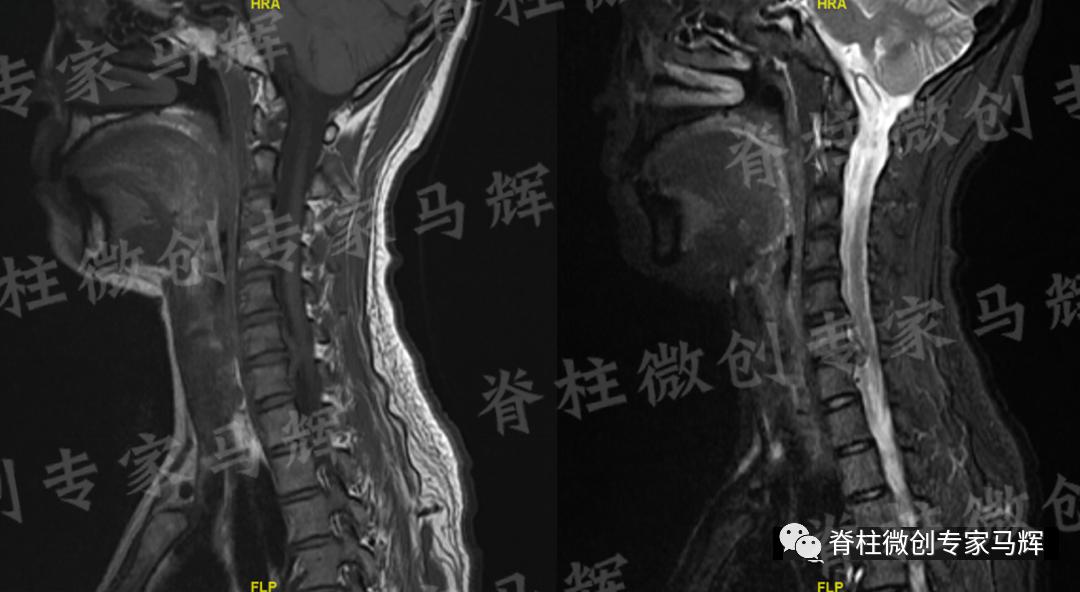

马主任仔细给患者做了检查,发现疼痛范围累及颈背部,及右上臂、前臂至手掌桡侧三指,无胸背部束带感,无行走不稳。根据影像学结果,诊断缪女士患6/7椎间盘突出症,属于神经根型颈椎病。

(术前)